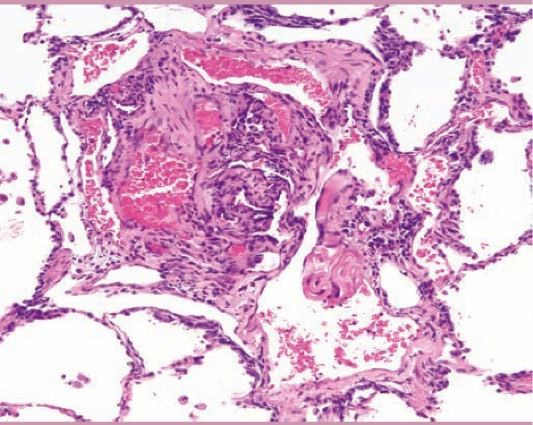

1046. Пациентке 36 лет с одышкой при физической нагрузке и легочной гипертензией в анамнезе выполнили пневмонэктомию, при гистологическом исследовании обнаружены следующие изменения диагноз _____ наиболее вероятен